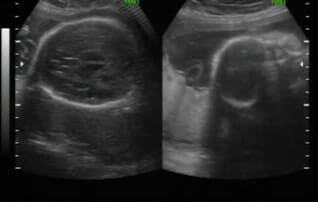

3D-Ultrasound